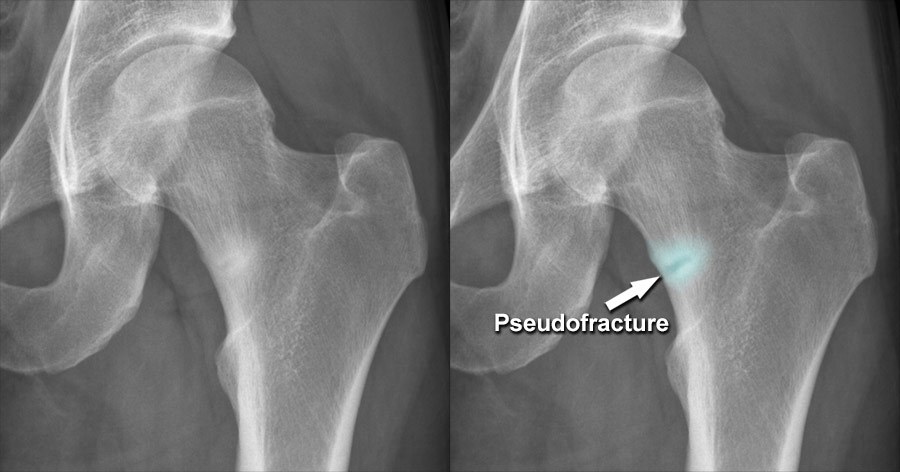

tumors secrete FGF-23 and cause hypophosphatemia through renal phosphate wasting. Chronic hypophosphatemia leads to osteomalacia that appears as osteopenia and pseudofractures on radiographs.

Image from: radiologymasterclass.co.uk